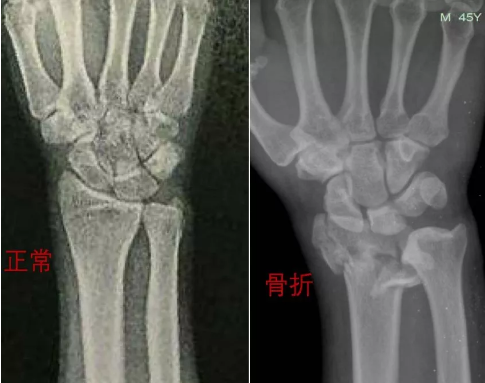

手腕骨折正确睡姿图,手腕骨折睡觉图

骨科知识 | 手腕骨折了该怎么办?

中医正骨就是这么神奇——部分骨折中医正骨前后照片对比(第三期)